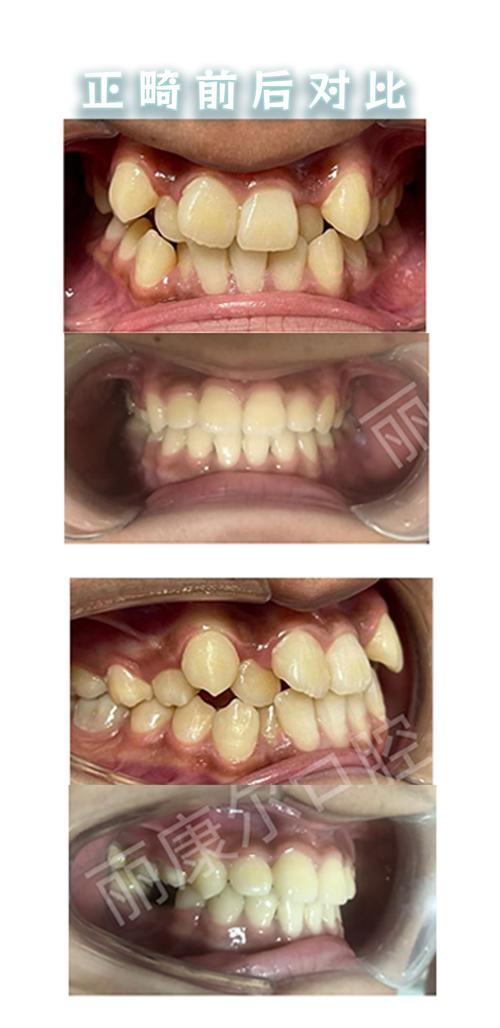

牙齿正畸是常见的口腔治疗方式,通过矫正装置调整牙齿排列和颌骨关系,改善咬合功能与面部美观,在正畸治疗前,全面的口腔检查必不可少,其中X光检查是评估口腔内部情况的关键手段,当女性处于怀孕这一特殊生理阶段时,牙齿正畸与X光检查的关联便需要格外谨慎对待,涉及胎儿安全、治疗效果及孕期口腔健康管理等多重问题。

- 牙龈敏感与炎症:孕期激素变化使牙龈血管扩张、通透性增加,易引发妊娠期牙龈炎,表现为牙龈红肿、出血,若此时佩戴固定矫治器(如托槽、弓丝),食物嵌塞和口腔清洁难度增加,可能加重牙龈炎症。

- 暂停正畸加力:孕期不建议进行牙齿主动移动(如调整弓丝、更换橡皮筋),以免因激素影响导致牙根吸收或骨损伤,若已佩戴矫治器,需加强口腔清洁,避免牙龈炎。